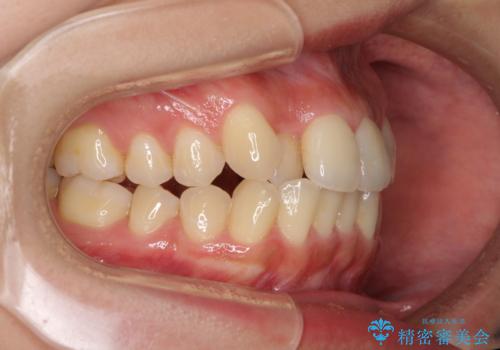

より治療を速やかに行うため、上顎右側にアンカースクリューを使用し、目標としていた1年半ほどで治療を終えることができました。